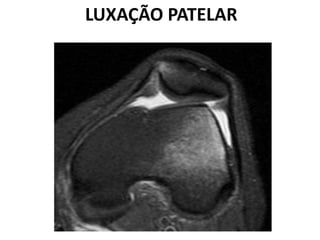

LUXAÇÃO PATELAR

CONDROMALÁCIA PATELAR

 Lesão na cartilagem articular até a superfície óssea devido

ao excesso de forças de cisalhamento entre a patela e a

porção distal do fêmur.

 Comum em jovens e adultos.